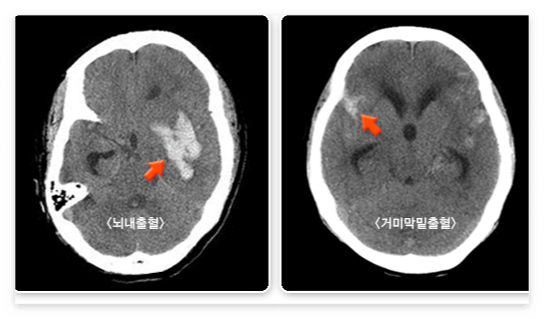

뇌출혈에는 뇌내출혈과 거미막밑출혈 등이 있습니다.

- 뇌내출혈

갑자기 뇌내 혈관이 터지면서 뇌 안에 피가 고이는 병입니다. 이의 대부분은 고혈압이 원인이다. 오래된 고혈압은 뇌내 소혈관을 손상시킬 수 있는데, 손상된 뇌혈관은 스트레스나 압력에 취약해져 잘 터질 수 있습니다. 이 외에 뇌혈관 기형이나 모야모야병에서도 혈관이 약해져 뇌출혈이 발생할 수 있다.

- 거미막밑출혈

뇌 동맥의 한 부분이 꽈리처럼 부풀어 올라 생긴 것을 동맥류라고 합니다. 동맥류 부위는 혈관벽이 약해서 잘 터질 수 있는데, 이 경우 피는 뇌를 싸고 있는 거미막(지주막) 밑에 고이게 된다. 따라서 출혈 발생 초기에 뇌내 조직의 직접 손상은 심하지 않아, 다른 신경학적 증상보다는 심한 두통과 구토가 특징입니다.